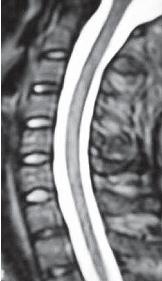

На МРТ № 47 наблюдается сглаженность лордоза с незначительной кифотизацией, которая привела к абсолютному стенозу спинномозгового канала и блоку ликворных путей, а также протрузии в сегменте СIV-СV, вентральному спондилёзу в сегменте CV-CVI и остеофитозу в сегменте CVI-CVII, гипертрофии передней и задней продольных связок. Это наиболее значительные проблемы в данном отделе. ![]() На МРТ № 48 наблюдается сглаженность лордоза, но без кифотической деформации, снижение высоты межпозвонковых дисков, протрузии в сегментах CV-CVI и CVI-CVII, частично компенсированные спондилёзом, выражены краевые остеофиты на данном уровне, абсолютный стеноз и блок ликворных путей, гипертрофия передней и задней продольных связок. ![]() На МРТ № 49 наблюдается кифоз шейного отдела позвоночника, хотя он и не привёл к абсолютному стенозу спинномозгового канала позвоночника, однако значительно нарушил ликвородинамику. Вентральное эпидуральное пространство блокировано вершиной кифоза с экскавацией и оттеснением спинного мозга, а дорсальное эпидуральное пространство блокируется чуть ниже от вершины задней стенкой спинномозгового канала. МРТ № 50